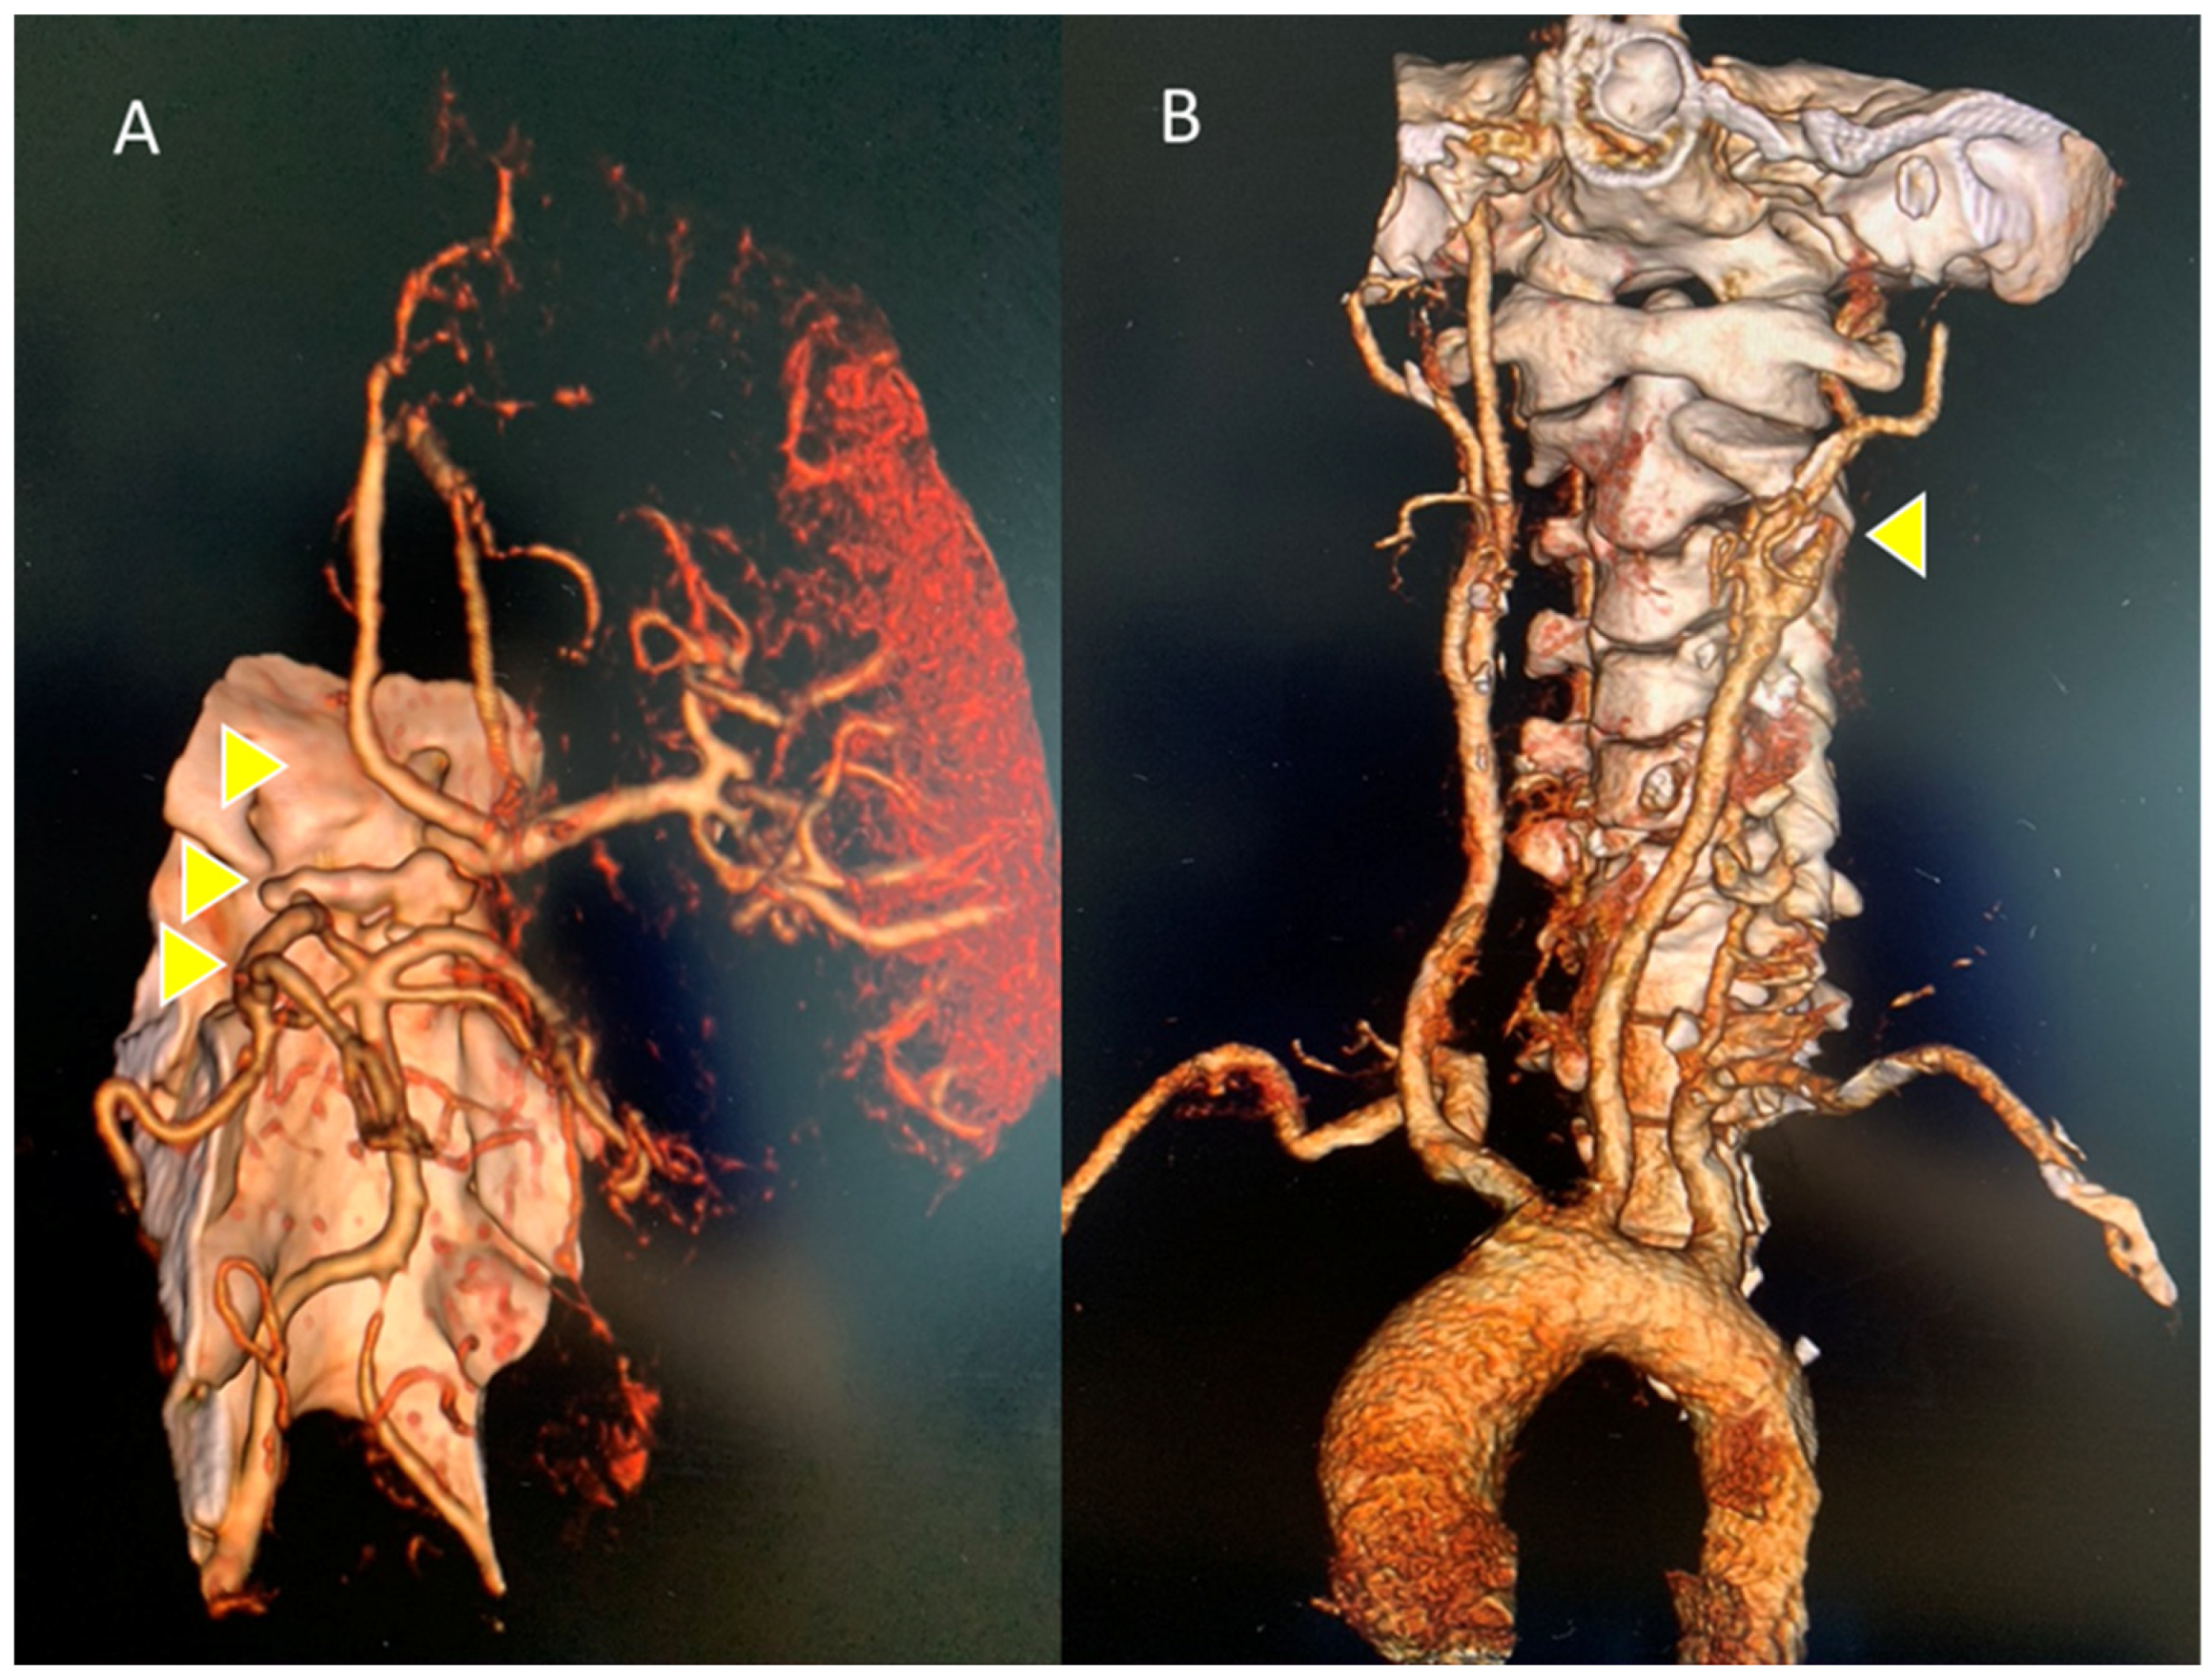

2. Detailed Case Description